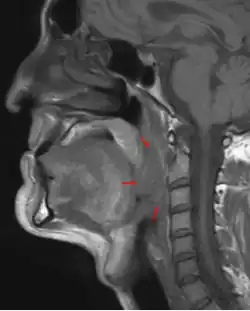

Oropharyngeal cancer (from right tonsil, HPV-negative), T4a N2c, 48-year-old man